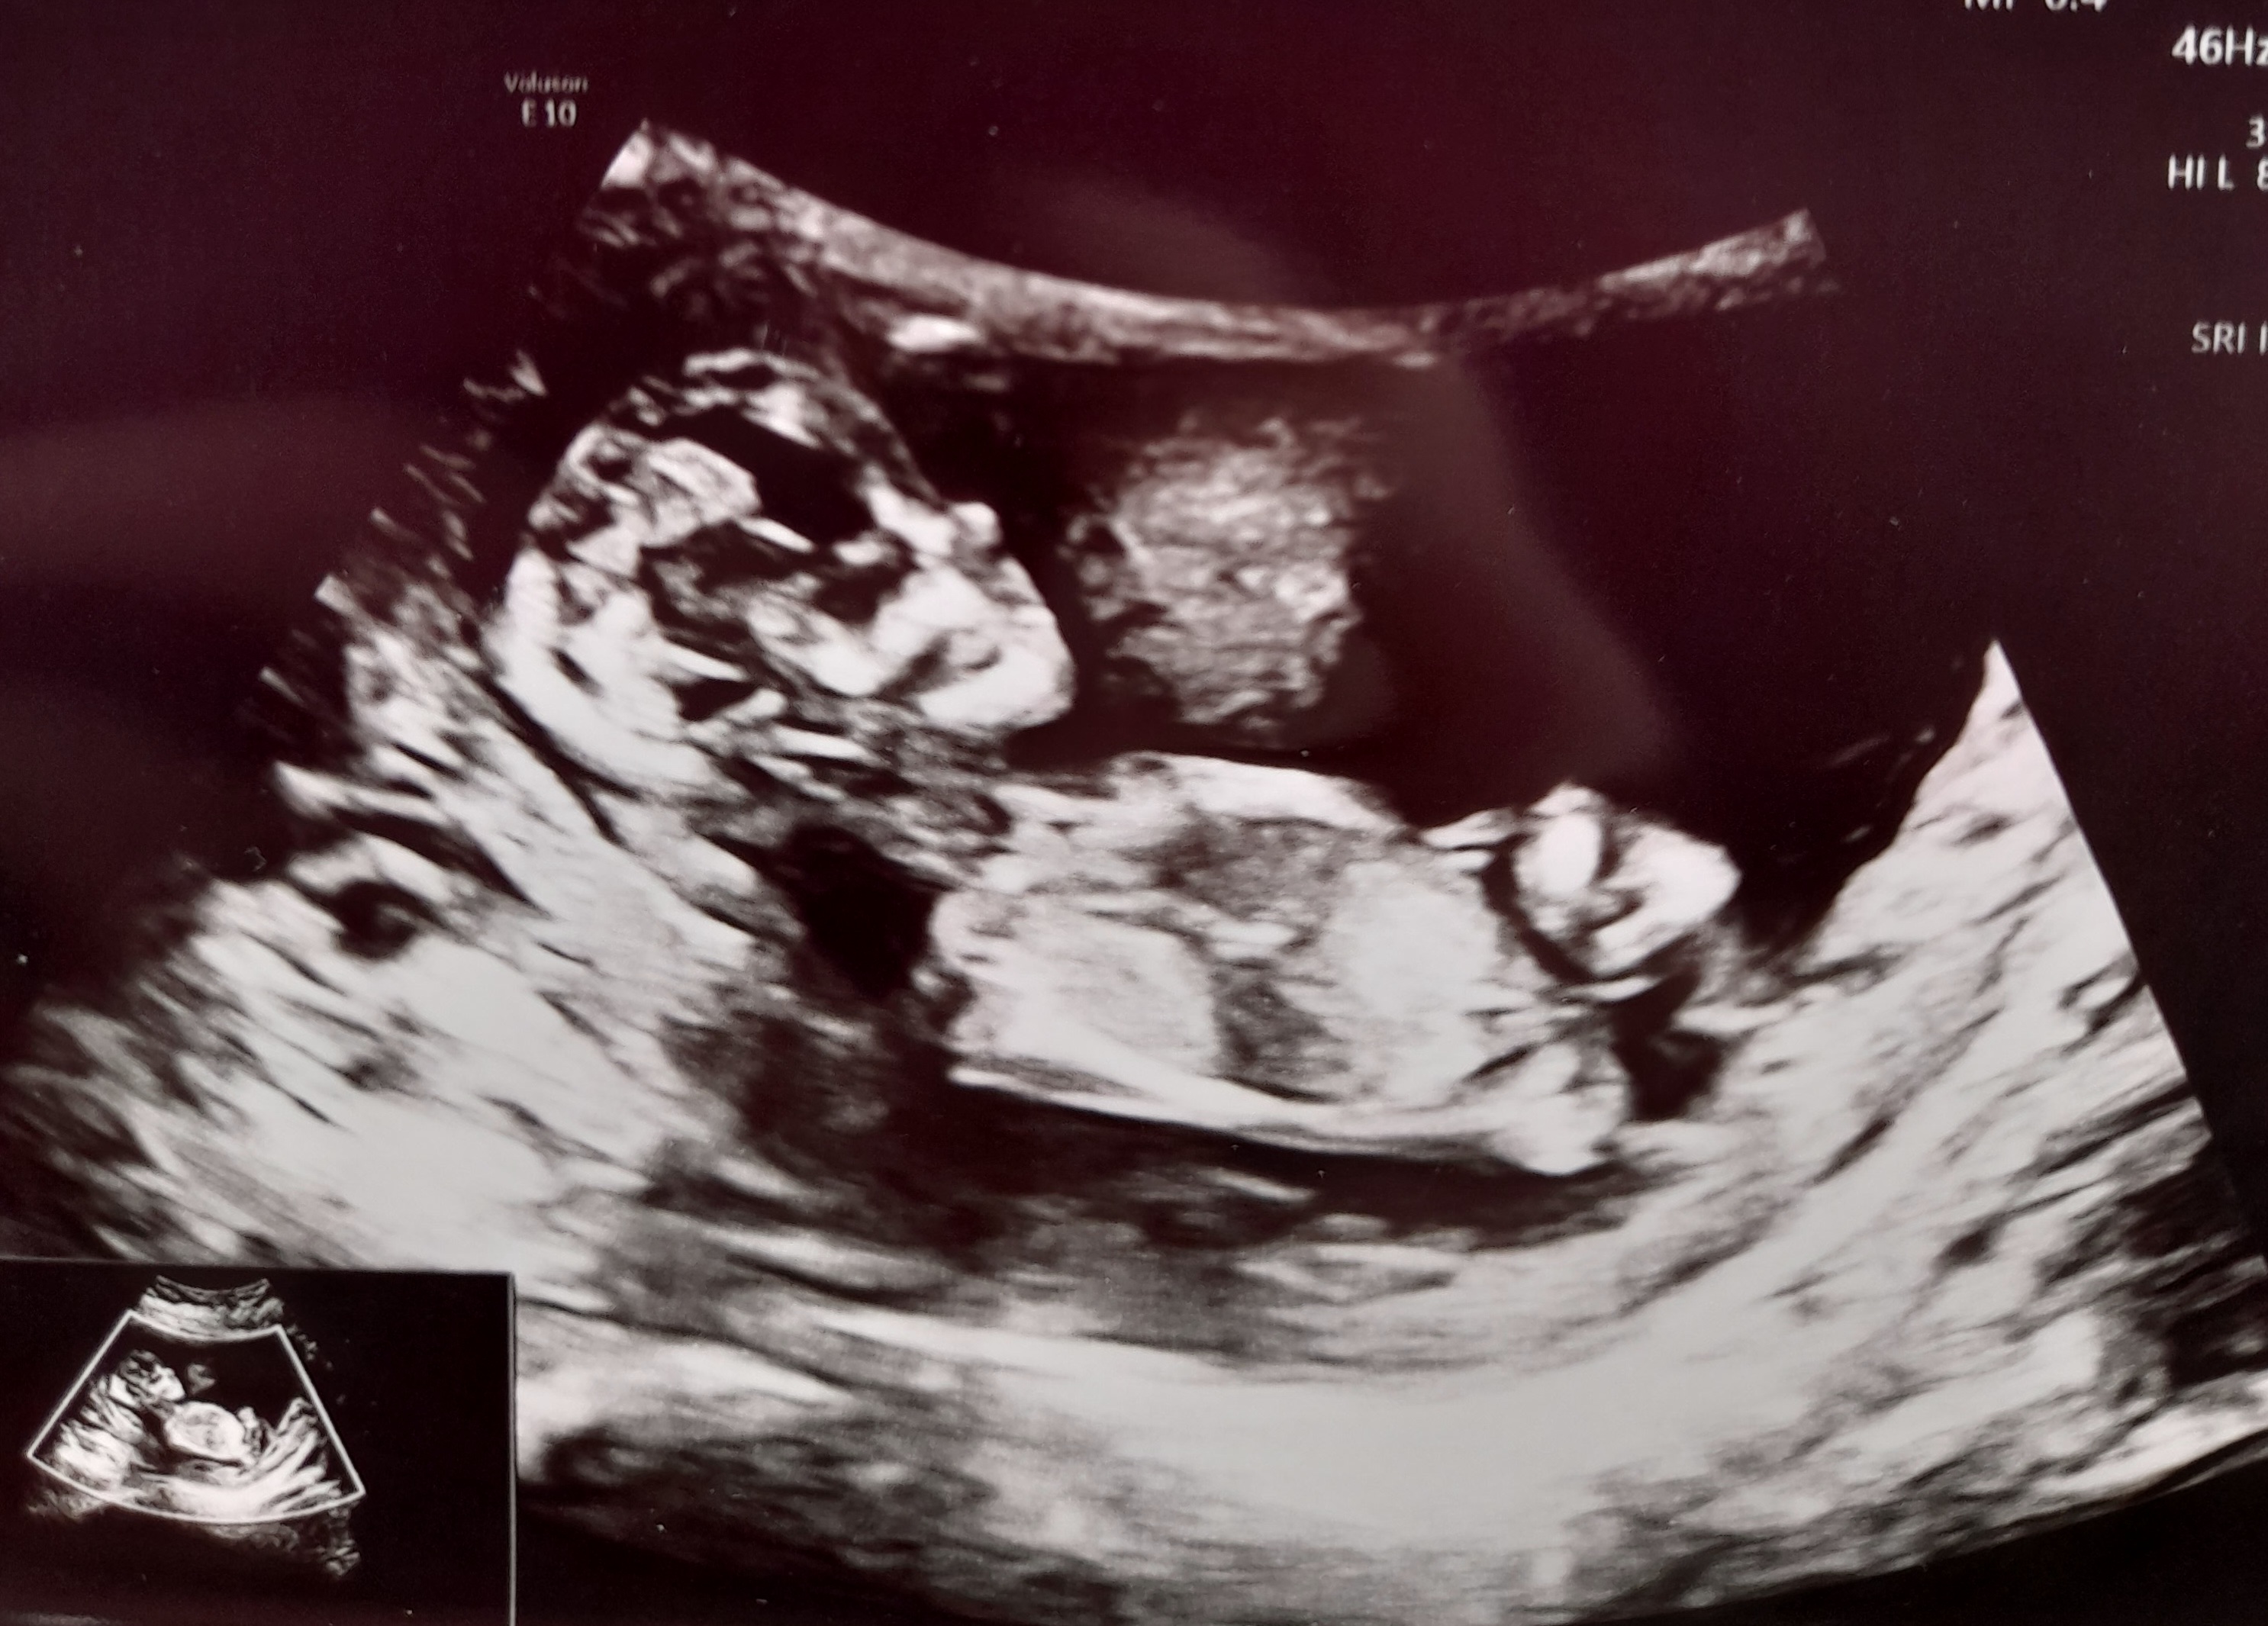

13+2

Tusen takk alle sammen❤️ Tankene deres hjalp masse på veien til sykehuset. Vi hadde time kl 10.00 og alt gikk bra!

Jeg holdt pusten omtrent da jordmor startet opp og fant Lille med en gang. Husbonden snufset litt og etterhvert som undersøkelsen skred fram og boks etter boks ble krysset av med 'normalt' så begynte tårene å renne hos meg og. Alt så fint ut og vi ble satt litt fram, fra 12+6 til 13+2.

Jeg spurte om kjønnet, men det mente JM det var for tidlig å se ennå. Tror ikke bildene viser noe, men et øyeblikk helt på slutten syntes jeg det så ut som nuben var veldig lett synlig så nå blir det spennende å se hva framtiden viser :joyful: :love017 ❤️